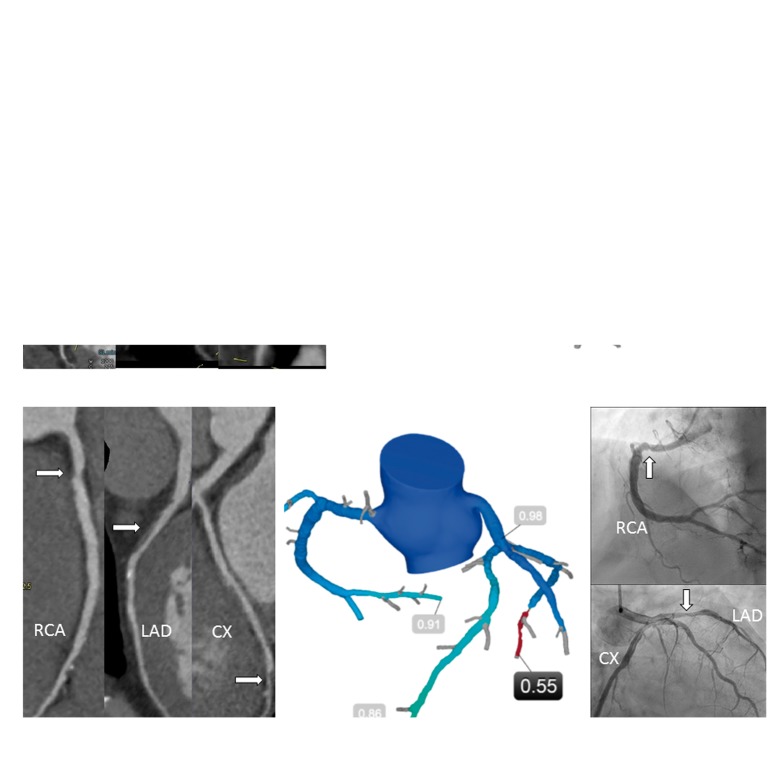

Figure 3.

(A) 66-year-old female. Typical angina. Left: Coronary CTA, moderate stenosis in RCA and LAD (arrows). Right: FFRCT 0.85 (RCA) and 0.90 (LAD). OMT was recommended. (B) 61-year-old male. Typical angina. Left: Coronary CTA, moderate stenosis in RCA, LAD, and CX (arrows). Centre: FFRCT 0.91 (RCA), 0.86 (LAD), 0.55 (CX). The patient was referred to ICA (Right): CX was stented and FFR was measured: 0.84 (LAD) and 0.90 (RCA). CTA, CT angiography; ICA, invasive coronary angiography; OMT, optimal medical treatment; FFRCT, prescribed coronary CTA derived fractional flow reserve; RCA, right coronary artery; LAD, left anterior descending coronary artery; CX, circumflex coronary artery.